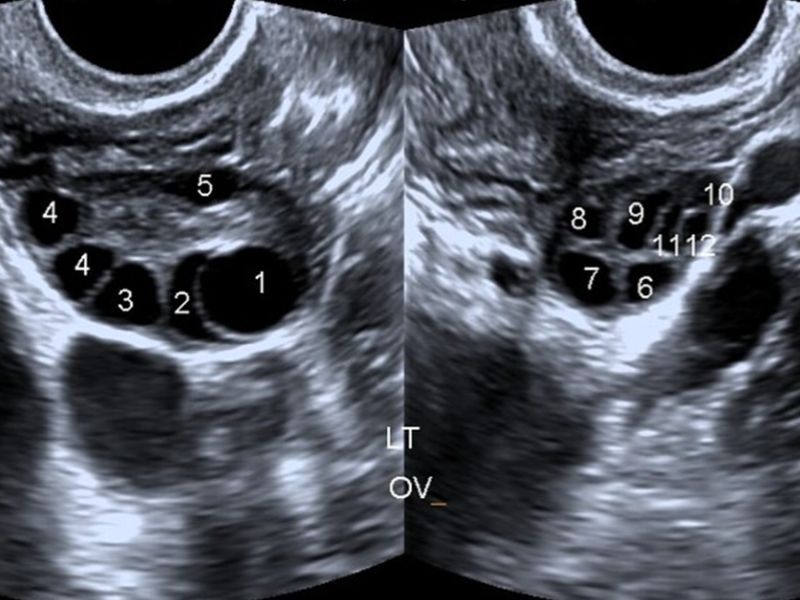

- Hình ảnh buồng trứng đa nang trên siêu âm, đó là buồng trứng có nhiều nang nhỏ (thường ≥ 12 nang mỗi bên), nang sắp xếp dọc ngoại vi buồng trứng, tăng thể tích buồng trứng, siêu âm qua đường âm đạo cho kết quả chính xác hơn

Họ cũng có thể thực hiện siêu âm để kiểm tra xem có nang trong buồng trứng và đo độ dày niêm mạc tử cung. Với siêu âm qua ngã âm đạo, bác sĩ sẽ đặt một đầu dò vào âm đạo để tạo hình ảnh chi tiết của cơ quan sinh sản.